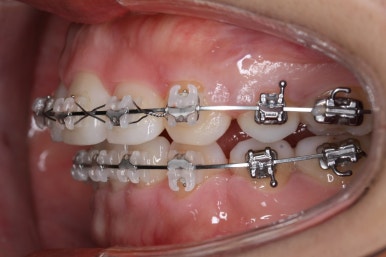

입안 모습입니다.

윗니와 아랫니 모두 각각 보면 가지런해 보이며 발치를 했던 자리도 거의 다 메워져서 양호해 보입니다. 훑어 보면 굳이 더 교정을 해야할 부분이 있을까? 싶겠지만 다음 사진을 보면 알 수 있습니다.

입 속 좌우 모습인데요. 문제점은 다음과 같이 있었어요.

윗니와 아랫니의 교합이 톱니바퀴처럼 맞물리지 않고 1대1 정면으로 맞닿고 있었습니다.

앞니쪽도 보면 윗니와 아랫니의 앞뒤 간격이 크게 차이나는 것을 볼 수 있습니다.

발치교정을 하였을 때, 흔히 나타나는 문제인데 앞니의 각도가 안으로 매우 굽어져 있습니다. 옥니라고 하며 발치를 한 공간을 너무 당겨 넣다보면 발생할 수 있습니다.